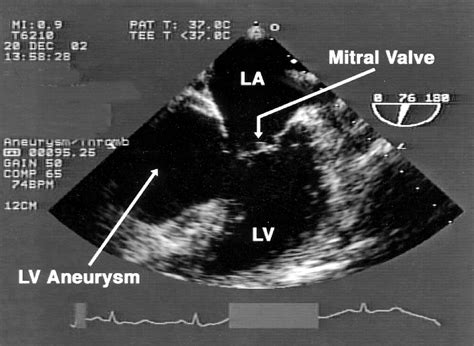

• Echocardiogram: This uses sound waves to create images of the heart, allowing doctors to visualize the aneurysm and assess its size and location.